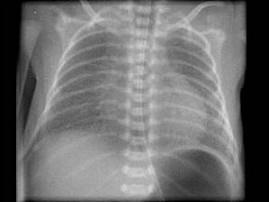

女,一天,呼吸困难、发绀,请结合图像选择最可能的诊断 ( )A、新生儿支气管炎B、肺不张C、新生儿肺炎D、法洛四联征E、呼吸窘迫综合征

选项 A、新生儿支气管炎 B、肺不张 C、新生儿肺炎 D、法洛四联征 E、呼吸窘迫综合征

答案 E